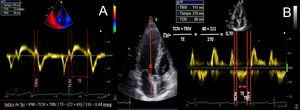

| C.2.2. Índice de Tei o índice de funcionamiento miocárdico (IFM) o índice de performance miocárdico. Permite hacer una estimación global tanto de la función sistólica como de la diastólica ventricular (derecha o izquierda). Está basado en la relación del trabajo eyectivo y no eyectivo del corazón. Se define como la relación entre la suma del tiempo de relajación isovolumétrica y de la contracción isovolumétrica, dividido por el tiempo eyectivo (índice Tei =TRIV +TCIV) /TE). Índice pronóstico poco utilizado en la práctica clínica, tendiendo a aumentar en caso de disfunción ventricular sistólica y/o diastólica.Es un método simple de obtener, reproducible, independiente de la frecuencia cardíaca y de la presión arterial, y es útil para estimar la severidad y el pronóstico de la afectación miocárdica y como predictor de disfunción postoperatoria ventricular izquierda en pacientes con insuficiencia mitral con fracción eyectiva aparentemente normal (4). Un índice Tei preoperatorio >0,5 permite predecir la disfunción postoperatoria del VI en pacientes con IM con FE aparentemente normal. Podemos medirlo mediante Doppler tisular a nivel del anillo mitral (A) o Doppler espectral pulsado, colocando el volumen de muestra amplio entre el TSVI y la mitral (B). El DTI puede utilizarse también para medir el índice Tei del VD, teniendo en cuenta que el TRIV del VD es prácticamente inexistente en el VD normal. Es un parámetro no influido por la frecuencia cardiaca ni la precarga que ha demostrado correlación con la severidad y el pronóstico de diversas patologías que afectan al VD. Su valor normal por DTI es de 0,39, considerándose patológico cuando es superior a 0,55. | ||